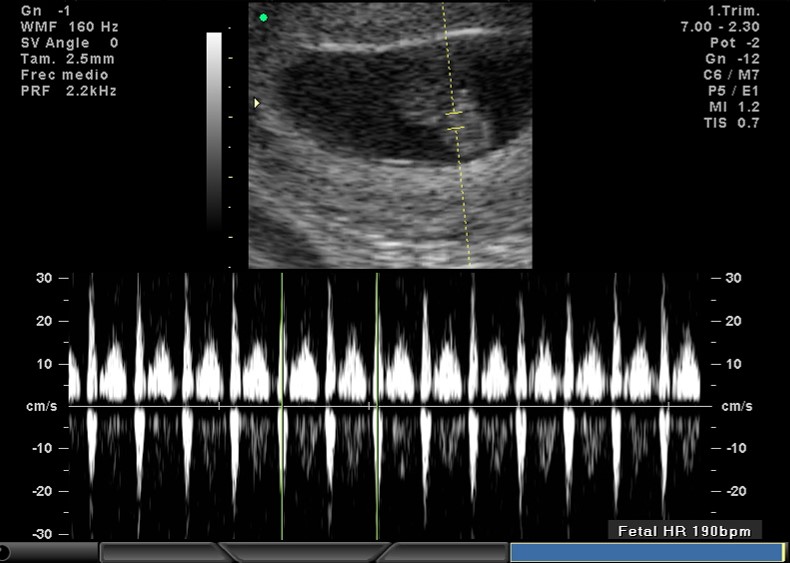

2D FRECUENCIA CARDIACA 10.5 SEMANAS